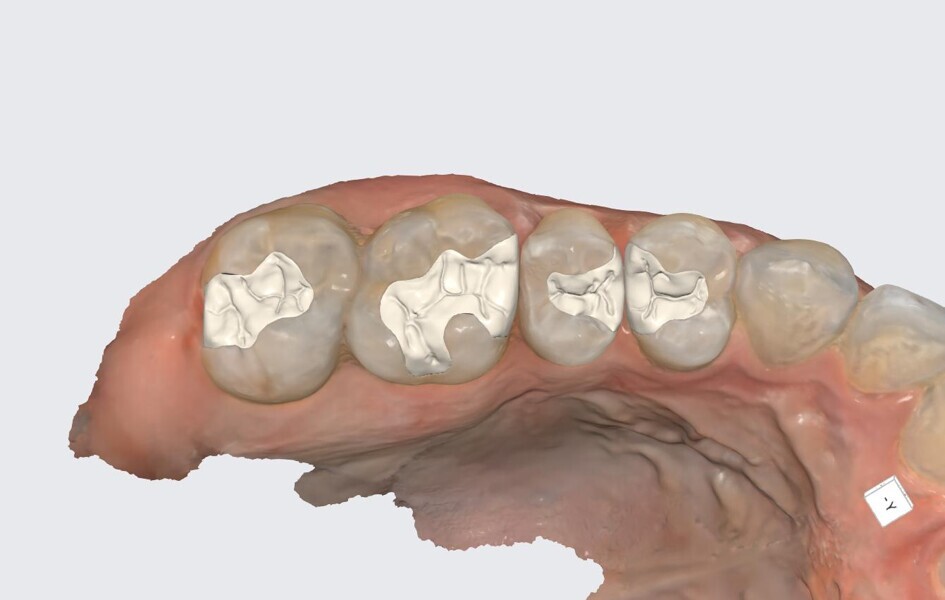

Figs. 24a–l: Virtual restorations from the occlusal view (a–d), buccal view (e–h) and intaglio view (i–l).

The prepared sextant and opposing dentition as well as the occluded arches were scanned with the Medit i900 and the scans imported into Medit ClinicCAD. The restorations were designed in the software with a cement gap of 0.1 mm and a minimum thickness of 0.6 mm to contours matching the preoperative treatment scan (Fig. 23). The virtual restorations were removed from the virtual models in preparation for 3D printing on the Midas printer (Fig. 24). Supports were added to the virtual onlays and the designs prepared for 3D printing.